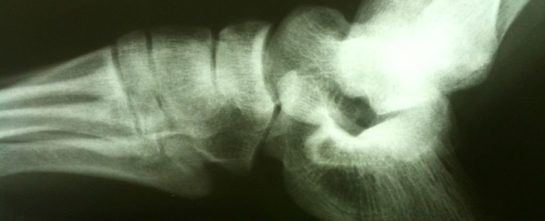

Ocho semanas después de la infusión de células madre, se evaluaron los casos de fracturas en fémur, tibia y huesos humorísticos en los 168 ratones tratados y 156 control.

El equipo encontró una disminución del 79% en la tasa de fracturas en los ratones tratados. Los huesos también fueron sometidos a pruebas de flexión, y se analizó su estructura y composición, las infusiones de células madre provocaron la liberaron de factores de crecimiento que hicieron que las células óseas existentes en los ratones se multiplicaran y maduraran más eficazmente.